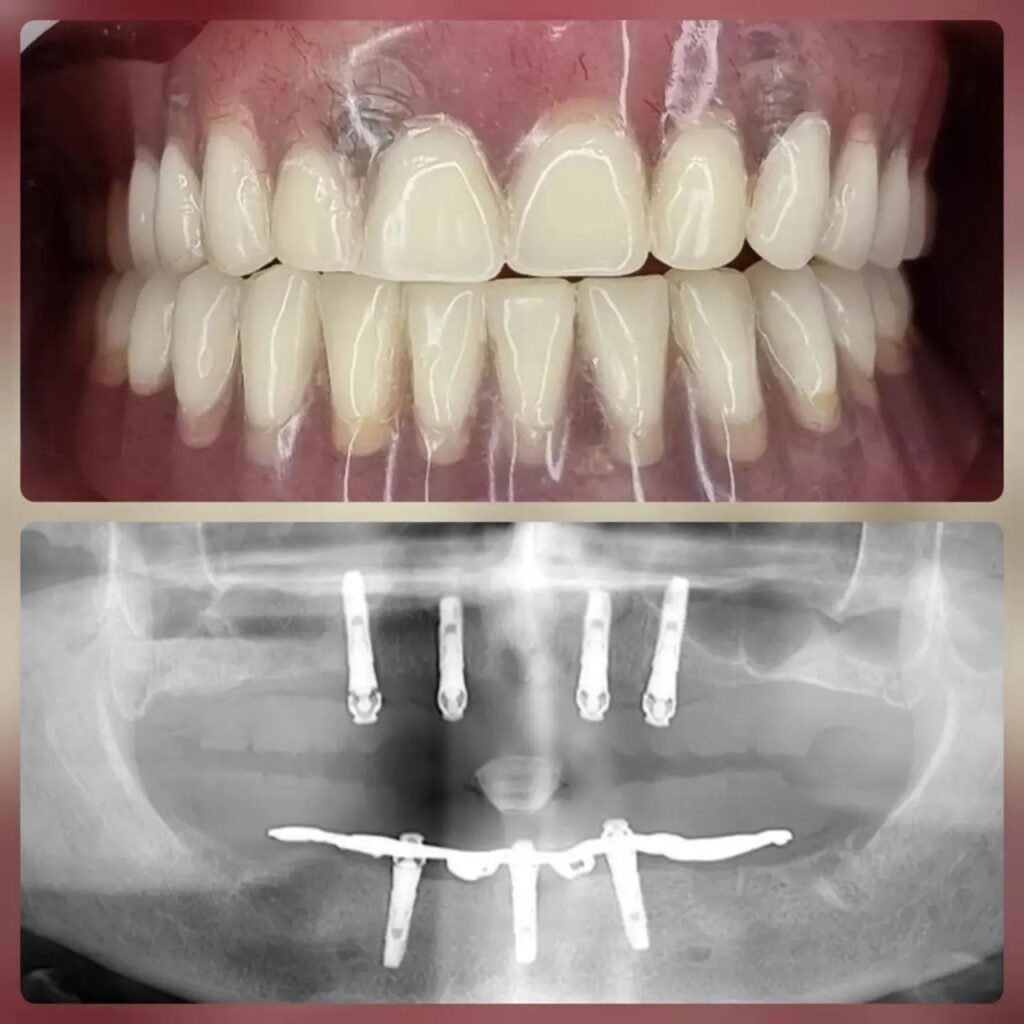

کاشت ایمپلنت دندان

اطمینان حاصل کردن از اینکه دندانهایتان به نحوی زیبا و طبیعی جایگزین شدهاند، از اهمیت بسیاری برخوردار است. ایمپلنت دندان به عنوان یک روش درمانی دائمی در دندانپزشکی شناخته میشود که حاصل آن، یک دندان زیبا و طبیعی در دهان شما خواهد بود.

هرچند که این روش درمانی هزینهی بیشتری نسبت به روشهای دیگر دارد، اما ارزش زیبایی که ایجاد میکند، قابل انکار نیست. ایمپلنتها به قدری شبیه به دندانهای طبیعی هستند که به سختی میتوان آنها را از دیگر دندانها تشخیص داد.